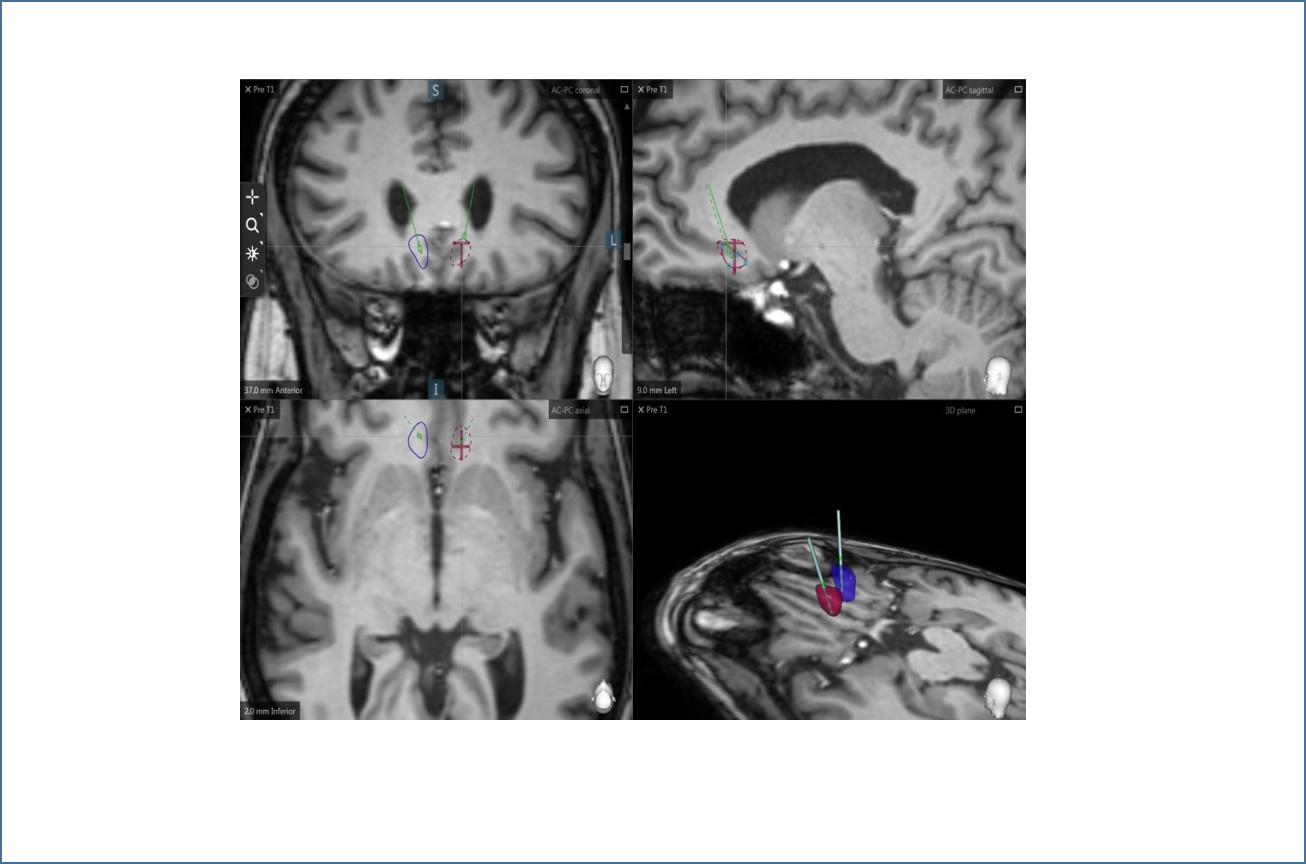

Colocación y programación de electrodos. Núcleo accumbens

Los resultados más destacados de este estudio piloto son la mejoría clínica en 4 de los 8 pacientes intervenidos, observándose una desaparición prácticamente completa de los delirios y alucinaciones, en dos de los pacientes en los que los implantes de electrodos se colocaron en una de las dos ubicaciones posibles en este ensayo, concretamente, en el núcleo accumbens, que forma parte de los llamados ganglios basales. Este porcentaje de respuesta del 50% es similar al hallado en otros estudios de DBS en enfermedades mentales, como la depresión o el TOC.